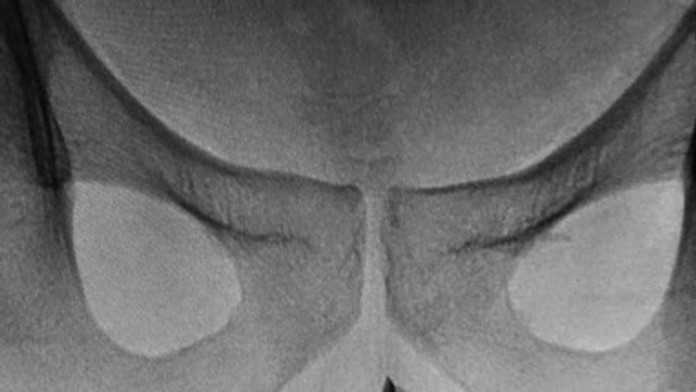

Netradičnú operáciu podstúpili lekári v Saudskej Arábii, ktorí museli mužovi vybrať z penisu takmer sedemcentimetrovú pinzetu.

Pacient bol počas zákroku v anestézii, pinzetu napokon vybrali kliešťami. Situáciu skomplikoval fakt, že pinzeta boli otvorená, a tak ju najskôr museli stlačiť. Keďže tlačila na telo, nedala sa vytiahnuť.